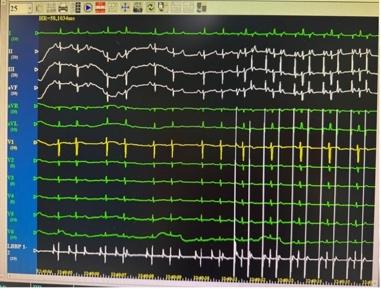

手术团队分两步精准构建了生理性起搏体系。首先成功行右心室左束支区域起搏(详见图2),使 QRS 波宽度缩至 93ms(达到健康人群正常范围),确保左右心室同步收缩,避免传统右室心尖起搏导致的心室不同步问题;随后团队将心房电极精准植入Bachmann束区域成功行Bachmann 束起搏,起搏时见P 波时限更高更窄(P波由 119ms直接缩短至 100ms,P波高度增加(详见图3、图4)。

图2:左束支区域起搏 图3 Bachmann 束起搏 图4 Bachmann 束电位

相较于传统起搏技术,该方案的优势集中体现在左束支区域起搏的基础上进一步实现了 Bachmann 束起搏:一方面,可显著降低术后房颤发生率(房颤是传统起搏患者常见远期并发症);另一方面,避免了传统右心耳起搏可能带来的右心耳穿孔、血栓形成等潜在风险,安全性与生理性兼具。

术后,患者心动过缓症状彻底改善,气短、乏力等不适消失,心功能逐步恢复。这得益于全生理性起搏的获益,更重要的是带来的心房同步传导,心室同步收缩,这大幅降低了她未来发生心衰、房颤的风险,为其后续高质量生活提供了 “心” 保障。